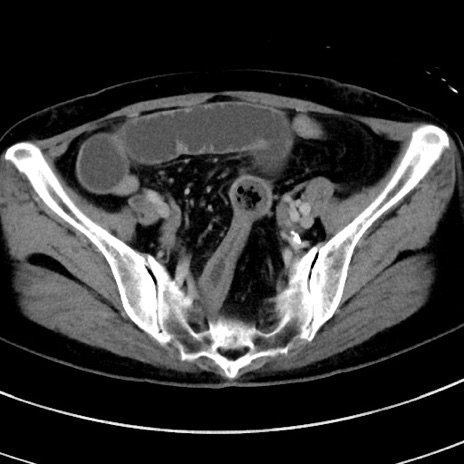

冠状断像

【症例】 60歳代女性

【主訴】むかつき、みぞおちの痛み

【現病歴】3日前よりむかつきがあり、食事がとれない。

【既往歴】糖尿病

【身体所見】発熱なし、心窩部圧痛軽度あるも、腹膜刺激症状なし。

【データ】WBC 7400、CRP 1.92